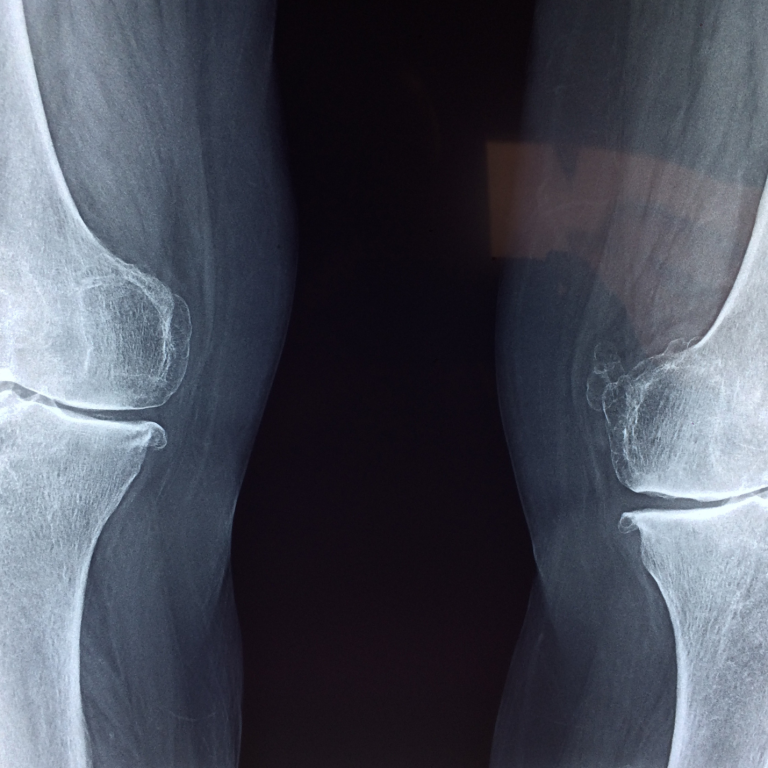

Osteoporosis is a condition that weakens bones, making them fragile and more likely to break. It is often referred to as a “silent disease” because it typically progresses without symptoms until a fracture occurs. Affecting